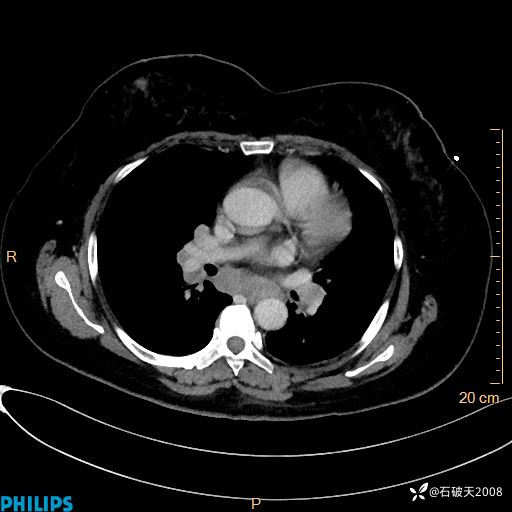

肺结节病?纵膈型肺癌?淋巴瘤?有点意思,欢迎围观

女 52岁 主 诉:咳嗽10余天,咳痰2天。

现病史:10余天前无明显诱因出现咳嗽,呈阵发性干咳,伴咽喉部发痒,无咽痛,无咳痰,无鼻塞、流涕、打喷嚏,无发热、畏寒、寒颤,无头痛、头晕,无胸闷、胸痛,无反酸、烧心,无腹痛、腹泻,无尿频、尿急,无皮疹等,在当地诊所求治,给予口服药物治疗(具体不详),病情无好转。遂在当地社区卫生服务中心开具口服药物治疗(具体不详),疗效欠佳。2天前出现咳痰,在我院门诊求治,行胸部CT提示肺部感染,建议住院,患者要求口服药物治疗,目前仍咳嗽、咳白色粘痰,白天量多,夜间自觉喉部喘鸣音,遂再次来院就诊,以“肺部感染”为诊断收入院。发病以来,神志清,精神可,饮食可,夜间睡眠差,大小便正常,近期体重无明显变化。

静脉期